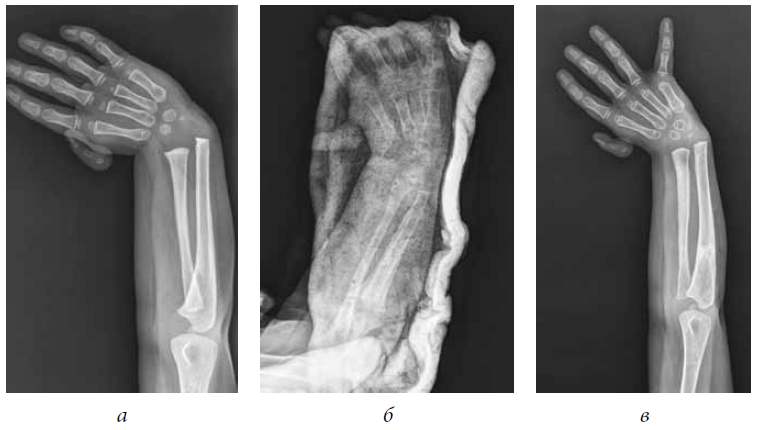

Patient A., 4 years old, was admitted to the department with diagnosis of congenital right-sided radial clubhand, i.e., hypoplasia of the first finger. He did not receive conservative or surgical treatment in a primary care facility. During clinical examination, right forearm shortening by 3 cm was noted, radial deviation of the hand was approximately 45°, the hand could not be passively brought to middle position, and first ray hypoplasia was observed (Fig. 2 a). Given the mild shortening of the radial bone compared with the ulnar bone and satisfactory development of the radial bone, it was decided to restore the radial bone by compression-distraction osteosynthesis. In the postoperative period, inflammation was registered around the exit site of transosseous elements, which were stopped by dressings with surface antiseptics and intake of oral antibiotics.

Fig. 2. Radiographs of the forearm of patient A., (a) 4 years before the surgical treatment, (b) after dismantling the external fixation device, and (c) after 1 year

After the removal of the external fixation device, thinning of the radial bone was established (Fig. 2 b). At 1-year follow-up, recurrence of hand deviation and shortening of the radial bone were registered (Fig. 2 c).